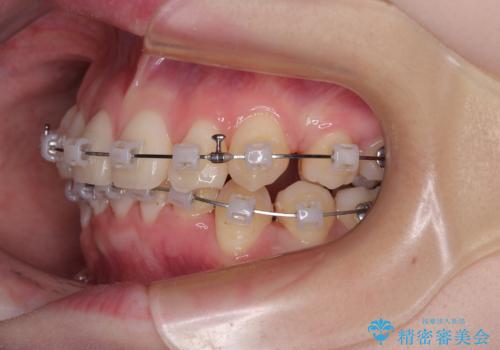

- クリアブラケット

上下ともに八重歯が顕著であり、前歯のクロスバイトがあったため、上下左右の第一小臼歯4本を抜歯し、ワイヤー装置での抜歯矯正を行うこととしました。

20歳ということもあり、歯の移動速度が非常に速く、1年強という短期間であっという間に治療を終えることができました。